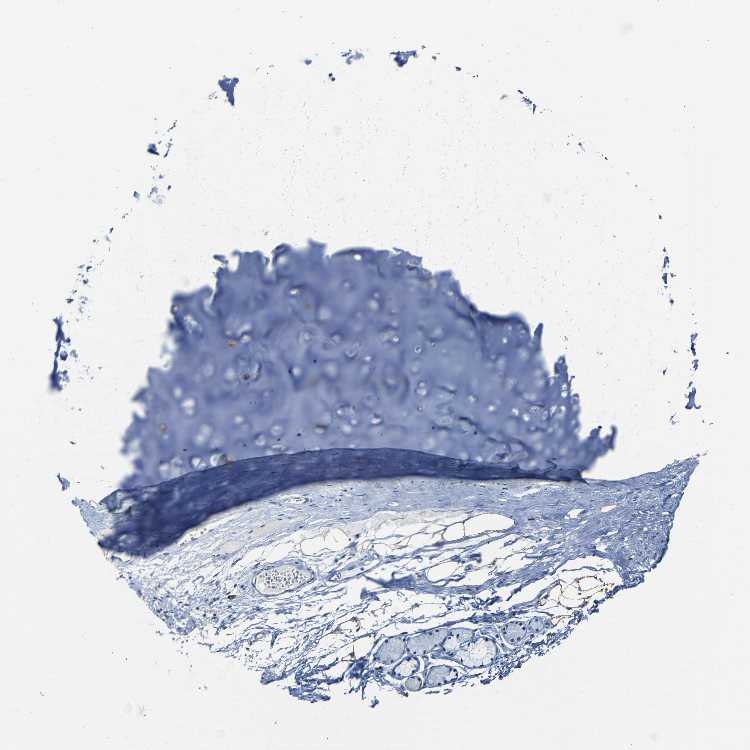

SOFT TISSUE 1 - Antibody stainingi

Antibody staining in the annotated cell types in the current human tissue is reported as not detected, low, medium, or high, based on conventional immunohistochemistry profiling in selected tissues. This score is based on the combination of the staining intensity and fraction of stained cells.

Each image is clickable and will lead to virtual microscopy that enables deeper exploration of all samples and also displays staining intensity scores, fraction scores and subcellular localization as well as patient and tissue information for each sample.

Antibody HPA013166Antibody CAB009789

Chondrocytes Low-

Fibroblasts Not detectedLow

Peripheral nerve Not detected-